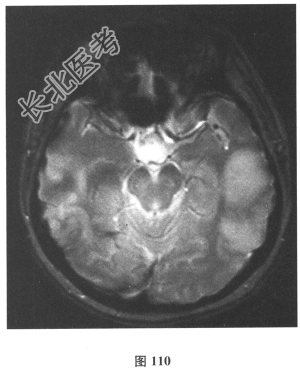

- 简答题2、脑脊液检查:常规、生化均正常,CSF-病毒TORCH(-),抗Hu、Yo、Ri均阴性,OB、MBP正常。血清抗Hu、Yo、Ri均阴性。颅脑MRI显示左颞枕、右顶枕多发长T₁、长T₂信号,Flair高信号,病变累及皮质及皮质下白质,病灶无强化,见图108~图114。)根据颅脑MRI,需要鉴别的疾病应是